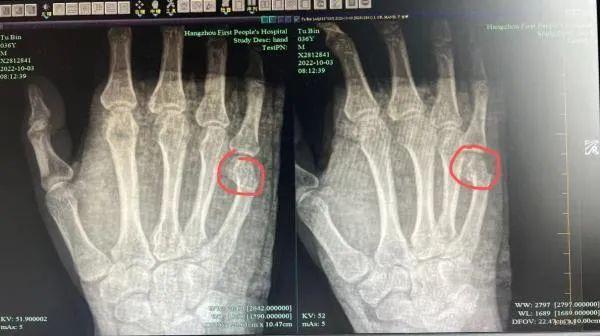

15/10/2022 21:51Bố gãy tay vì kèm con làm bài tập về nhà

Tình huống hi hữu mà ông bố gặp phải trong lúc dạy con học bài khiến nhiều người cảm thấy vô cùng bất ngờ.

Theo đó, câu chuyện hi hữu diễn ra vào ngày 11/10 vừa qua tại Hàng Châu, Trung Quốc, khiến nhiều bậc phụ huynh cảm thấy vừa đồng cảm lại vừa hài hước. Cụ thể, anh Ngô, 36 tuổi nhân một tối vợ vắng nhà đã phải kèm con trai học bài. Trong quá trình hướng dẫn con có một câu hỏi mà anh đã mất hơn nửa tiếng và giảng đi giảng lại nhiều lần nhưng cậu con trai vẫn không hiểu. Quá mất kiên nhẫn, anh Ngô lớn tiếng mắng con khiến cậu bé vùng vằng vứt bút không thèm làm bài tập nữa.

Hành động này của con trai như đổ thêm dầu vào lửa, thổi bùng lên cơn tức giận của anh Ngô. Trong một phút mất bình tĩnh, anh đã dùng tay đập mạnh xuống bàn và vô tình làm gãy bàn tay của chính mình.

Theo kết luận của bác sĩ, anh Ngô bị gãy ngón tay út bên phải, phần gãy bị lệch rõ ràng cần nhập viện điều trị ngay lập tức.